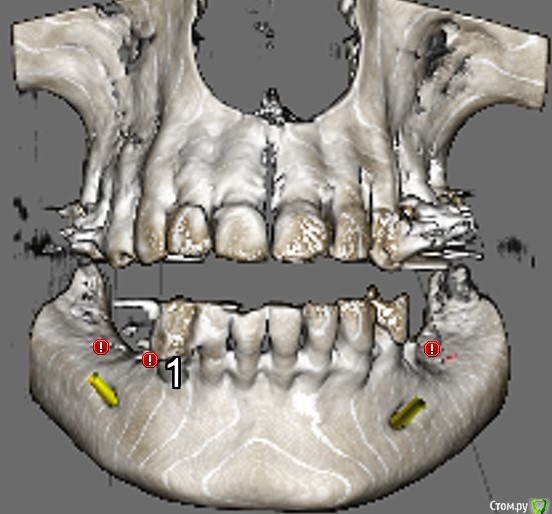

Вертикальная атрофия.

3й квадрант. Я могу обойти нерв. И даже выйти в более-менее приемлемую ортопедическую позицию.

Но очень смущает высота коронки и соотношение этой высоты к параметрам имплантата...